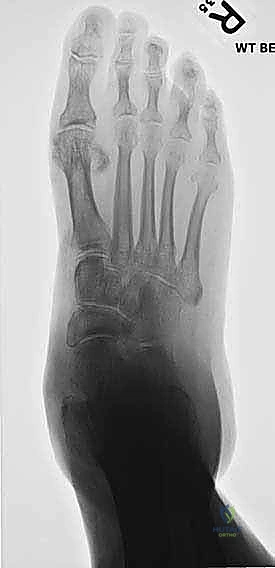

3. التصوير الشعاعي (X-rays): صور أشعة سينية أثناء الوقوف (Weight-bearing) لتقييم زوايا العظام ودرجة انهيار المفاصل.